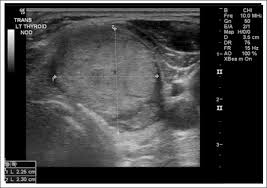

Symptoms of hyperthyroidism (weight loss, heart palpitations, sweating, nervousness, heat intolerance) if you have a thyroid nodule and you are younger than 20 years old or if you have a thyroid nodule and you are older than 70 let me be clear, though, just having these symptoms does not guarantee that you have thyroid cancer. For thyroid nodules that are too small to feel, this test can be used to guide a biopsy needle into the nodule to get a sample. A goiter is a term that describes an enlargement of the thyroid gland. Thyroid problems are caused by either too much or too little thyroid hormones in the blood. Thyroid cancer typically it first noticed as a thyroid nodule. Not all lumps are cancer, however. Thyroid cancer can cause any of the following signs or symptoms: Common in women thyroid disorders are more common in women, probably due to the roles of hormones, which are different in females than in males.

Most thyroid nodules do not produce any symptoms. (solid nodules are more likely to be cancerous.) it can also be used to check the number and size of thyroid nodules as well as help determine if any nearby lymph nodes are enlarged because the thyroid cancer has spread. Luckily, most of them are benign. The formations can press on blood vessels tightly. Thyroid cancer can cause any of the following signs or symptoms: Patients complain of the feeling of 'lump' and sore throat, difficulties with swallowing and/ or breathing, hoarseness or loss of voice, pain in neck. Thyroid disorders are more common in women. Thyroid nodules usually move up and down with swallowing. Not all lumps are cancer, however. A lump, nodule or swelling near the base of your neck that you can feel or see in the mirror is the most common symptom of thyroid cancer. When thyroid nodules become large (>4 cm or 1.5 in) they may cause symptoms by pressing on the airway or esophagus. A lump in the neck, sometimes growing quickly swelling in the neck pain in the front of the neck, sometimes going up to the ears Difficulty swallowing, hoarseness, or shortness of breath: